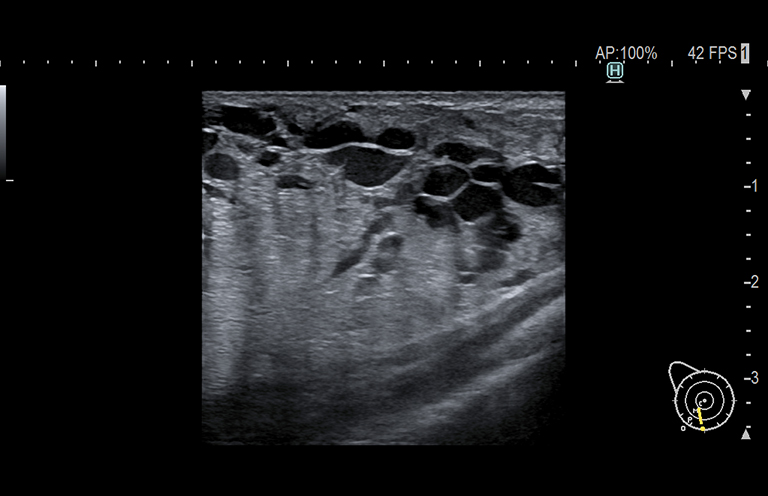

Aplicación: Mama

Función/análisis: Modo B

Comentarios: Mama